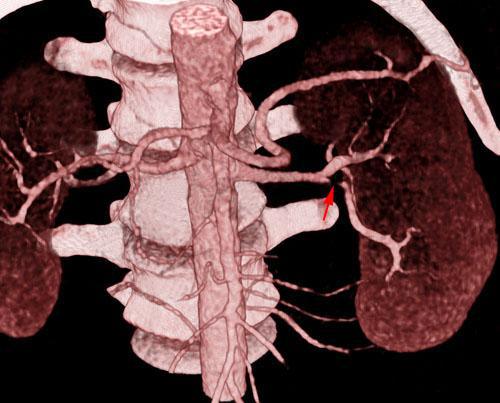

Estenosis moderada de arteria renal